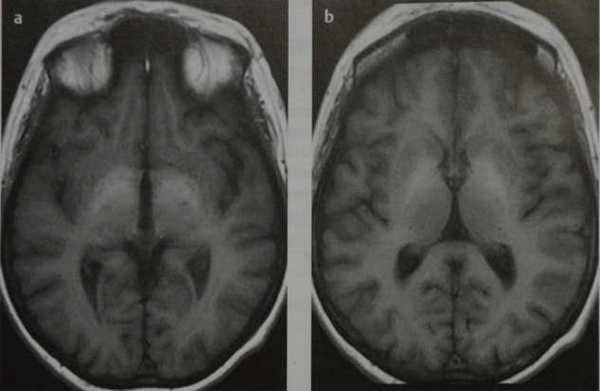

- На Т1-ВИ визуализируются двусторонние симметричные гиперинтенсивные зоны в базальных ядрах, изредка в хвостатом ядре, субталамическом ядре и в гипофизе (отложения парагмагнитного марганца)

Печеночная энцефалопатия. МРТ, нативные Т1-ВИ. Двусторонние симметричные гиперинтенсивные зоны в базальных ядрах.